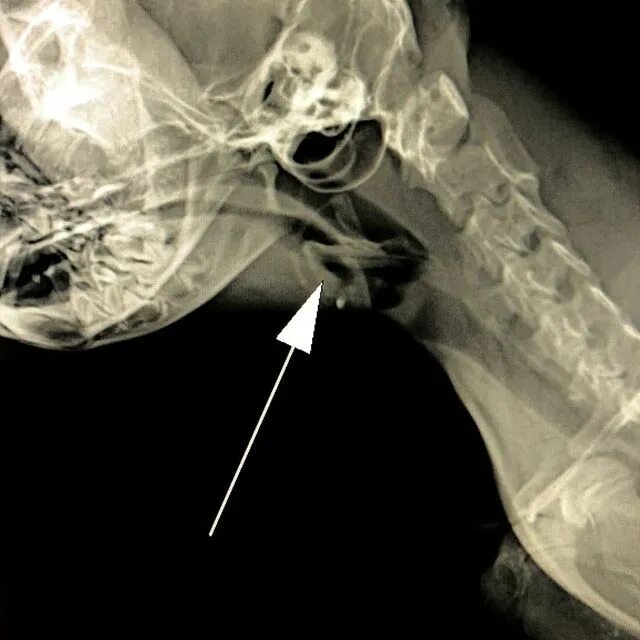

Как достать косточку из горла